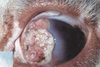

Mdx?

Entropion and secondary trichiasis